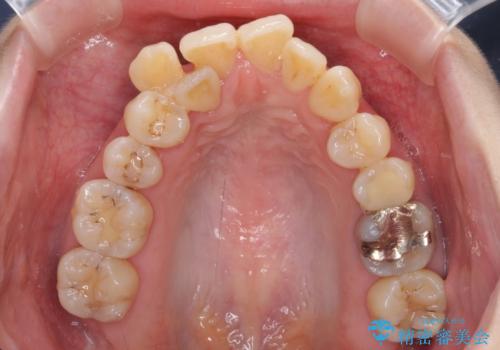

急速拡大装置 狭い骨幅を拡大した上で、顕著なデコボコを改善する抜歯矯正治療

- 前歯のデコボコと唇の閉じにくさを気にして来院された患者様です。

上顎骨よりも下顎骨の幅が広く、更には下顎骨が左側に変位していたため、より良い咬み合わせを達成することを目的として、急速拡大装置を用いて上顎骨を拡大することとしました。

デコボコが強い上に、口元の突出感も気にしていたため、上下左右の小臼歯4本を抜歯して、ワイヤー装置にて矯正治療を行うこととしました。

歯根露出が顕著であったため、歯の移動は早く、スムーズに治療を終えられるかと思いましたが、歯槽骨が硬く、治療は長期間に及びました。

過剰に力をかけ続ける事態となり、一部の歯では変色したり、神経が失活したりとトラブルが続きました。

それでも当初とは比べものにならないほど、綺麗な歯列に仕上げることができました。